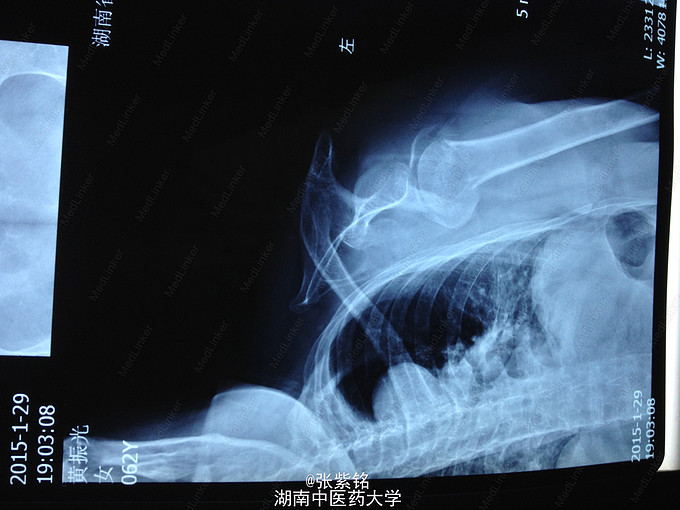

主诉:摔伤致左肩部肿痛,活动受限;头部疼痛伴活动性出血2小时余。 病史:在家中摔倒致伤左肩部、腰部及头部。症见:左肩关节及腰部肿痛,活动受限,精神一般,神志清,无畏寒、发热、头晕及呕吐等症状,二便正常。

查体见:左额部可见约2cm*2cm皮下血肿,并可见一不规则伤口约2cm,伴活动性出血。脊柱驼背畸形,胸椎后凸,头部前伸体态;颈、腰部旋转活动不能,腰部于L3-5椎体棘突处压痛明显,双下肢肌力、肌张力正常。左肩部关节明显肿胀,可扪及空虚感;局部压痛明显,左Dugas征阳性,左肩关节主动上举,外展,后伸,内收活动受限;被动活动患处疼痛加剧,左侧桡动脉搏动可扪及,皮肤感觉正常,左肘、腕及各指间关节血运感觉活动正常。 X线片示:左肩关节脱位,左肱骨外科颈骨折,左肱骨大结节撕脱性骨折。